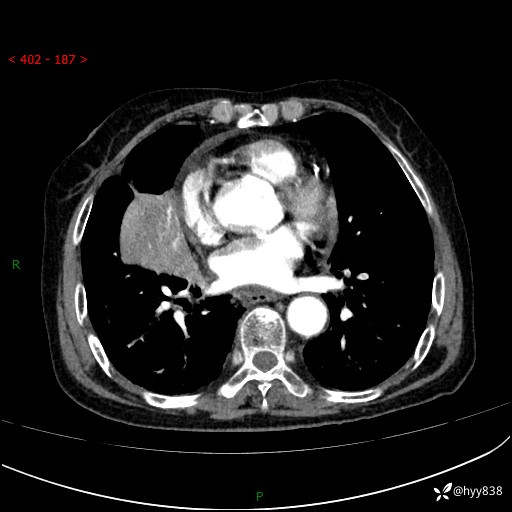

胸部CT增强(外院平扫)